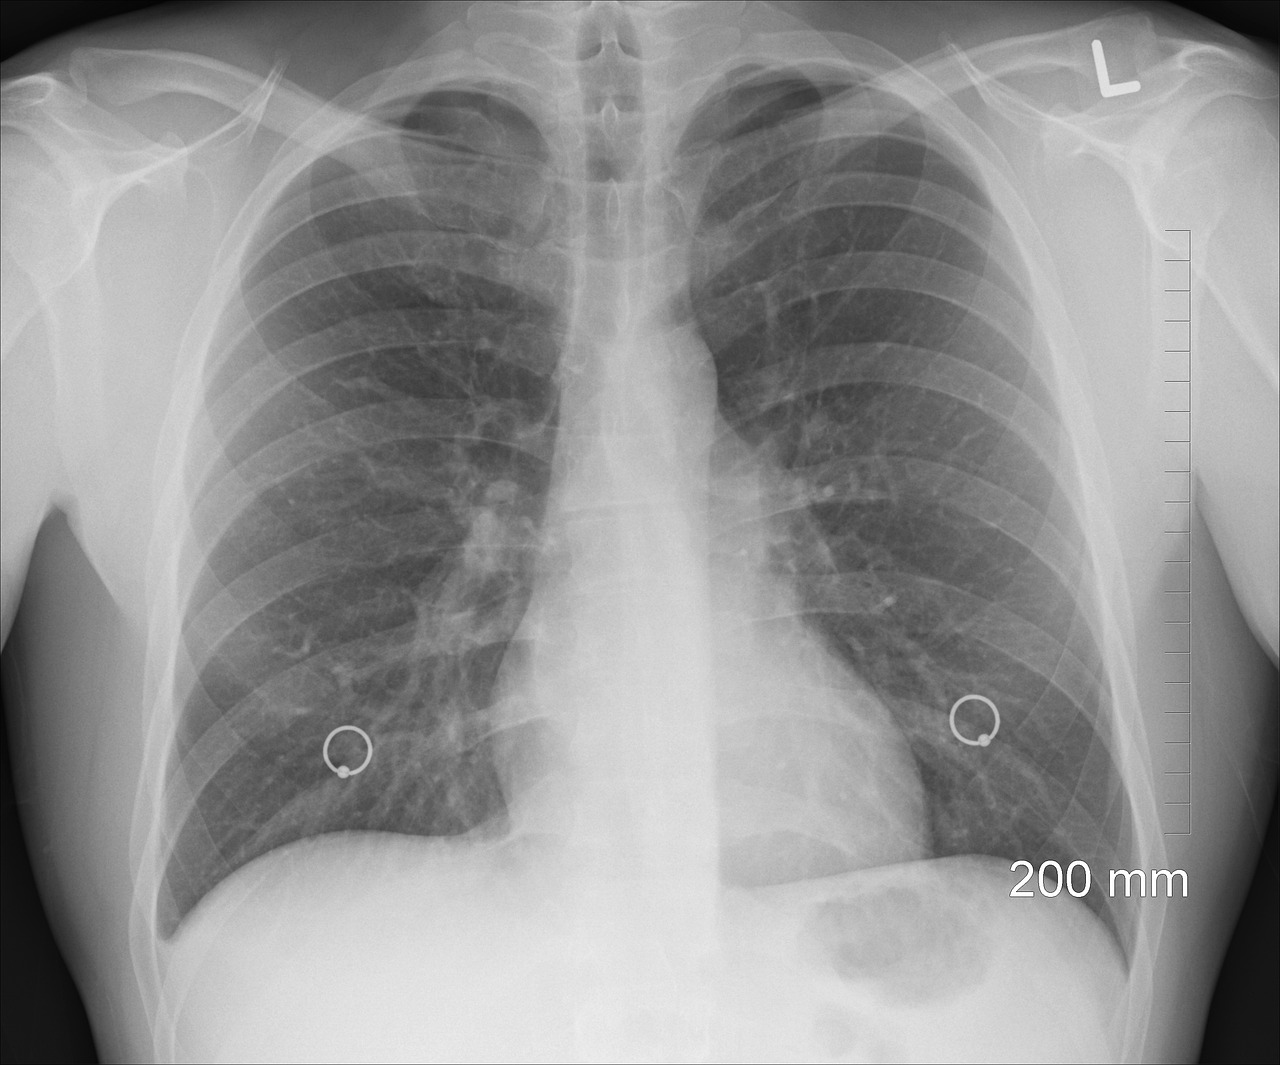

This excel template helps compare and evaluate SBRT lung plans per the guidlines in RTOG Protocol 0813. It has helped our clinic a lot as we compare trials for a specific patient as well as compare results from various tumor locations and of various shapes.

This is an excel spreadsheet used to evaluate SBRT plan.